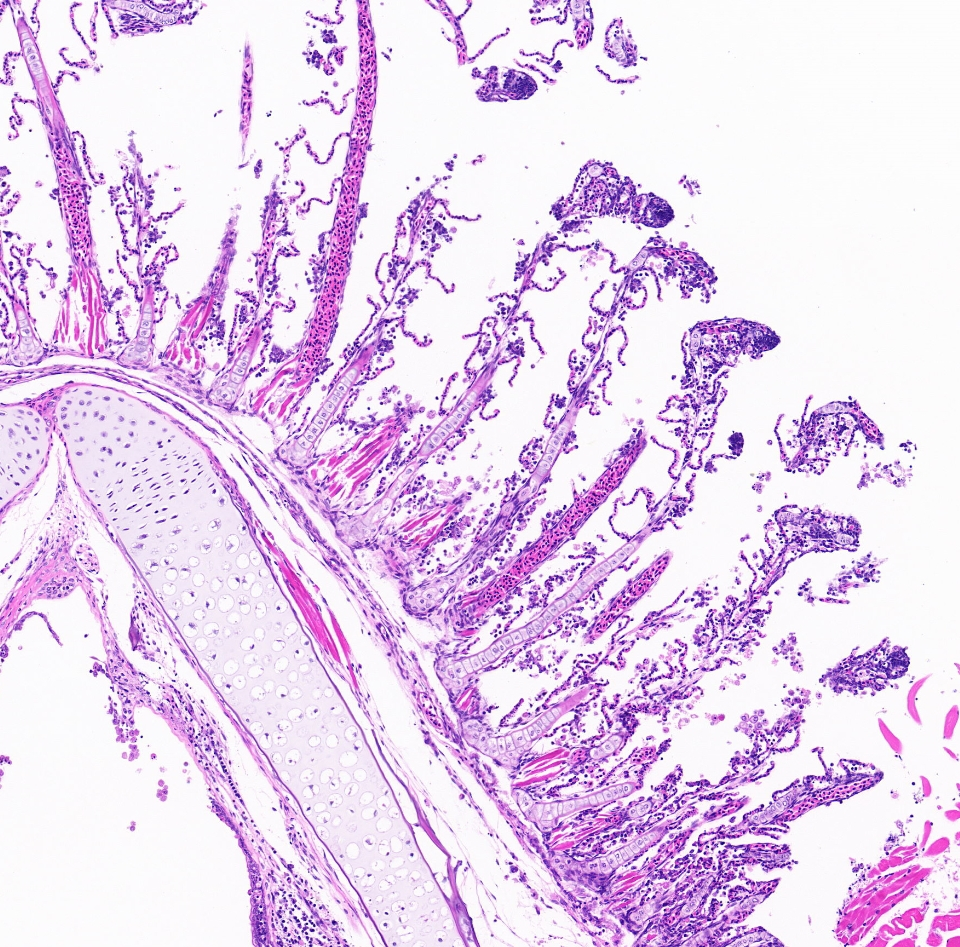

1. HE染色切片(动物组织):

苏木精-伊红染色法 ( hematoxylin-eosin staining ) ,简称HE染色法 ,石蜡切片技术里常用的染色法之一 。苏木精染液为碱性 ,主要使细胞核内的染色质与胞质内的核糖体着紫蓝色 ;伊红为酸性染料 ,主要使细胞质和细胞外基质中的成分着红色 。HE染色法是组织学、胚胎学、病理学教学与科研中最基本、使用最广泛的技术方法。